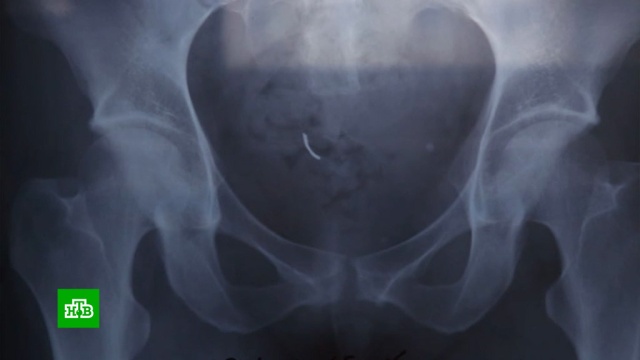

Младшему сыну Кристины Фоминовой 2,5 месяца. Но взять малыша на руки, ухаживать за ним, словом, окружить его материнской заботой, женщина пока не может — врачи запретили. У нее сейчас сложный реабилитационный период после операции, нужен отдых. Несколько часов врачи извлекали из ее тела хирургическую иглу, с которой ей пришлось прожить целых шесть лет. Все это время медики не могли найти причину сильных болей, которые мучили Кристину. Все стало понятно лишь после процедуры МРТ.

Кристина Фоминова: «Во время обследования через несколько секунд врач выкатил меня и с такими глазами сказал: „Я не могу продолжить обследование, у вас обнаружен металл в брюшной полости“».

К счастью, операция по извлечению иглы прошло успешно. И, когда самое страшное было уже позади, супруги все тщательно обдумали. В итоге пришли к выводу, что иглу в животе забыли акушеры